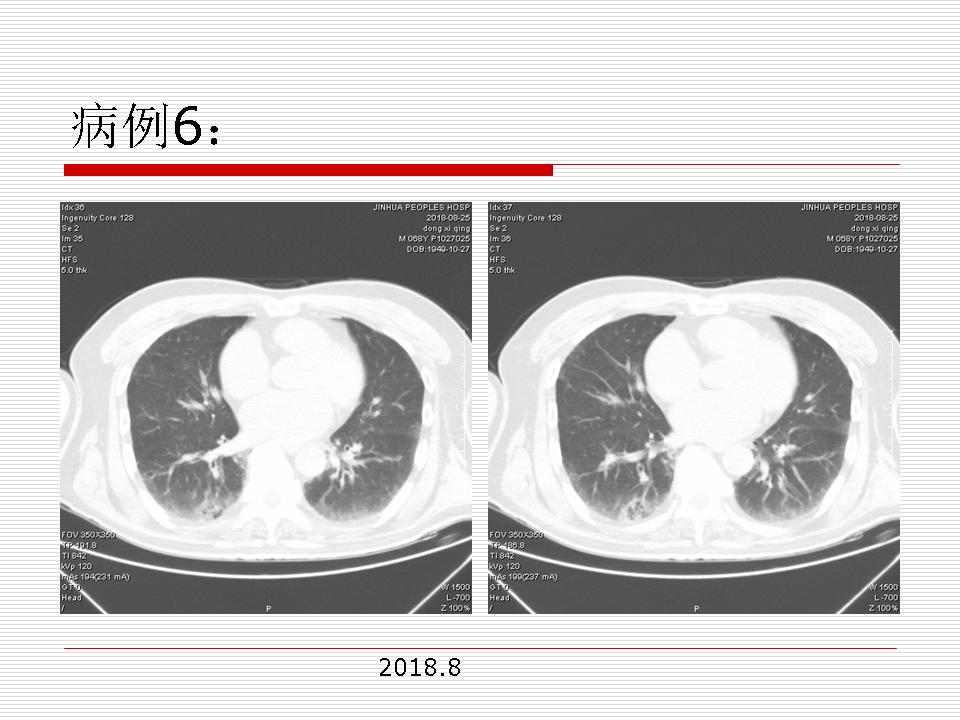

肺部阴影永恒且最重需要鉴别的是:到底是炎症还是肿瘤?但临床的病例中的影像表现难以界定或有些肿瘤特征,同时又有些炎症特点是非常常见的情况。作为临床医生我们怎么去总结分析,并找到之所以是炎症或之所以是肿瘤的细微差别或特点非常重要,也非常有用。2019.12.7浙江省2019年胸心外科学学术年会在宁波召开时,我的临床病例分析与经验总结<那些像肺癌的炎症与像炎症的肺癌>获得在大会交流的机会,以下为该PPT的内容,与你分享,希望对同道有益,有借鉴与启迪。若有探讨与进一不完善的建议,欢迎文末留言讨论: